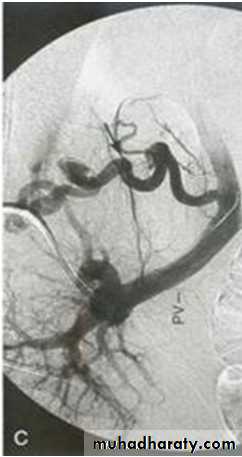

VARICES• THREE common areas of portal/caval anastomoses

• 100% related to portal hypertension

• Found in 90% of cirrhotics

• MASSIVE, SUDDEN, FATAL hemorrhage is the most feared consequence

Esophagial Varices